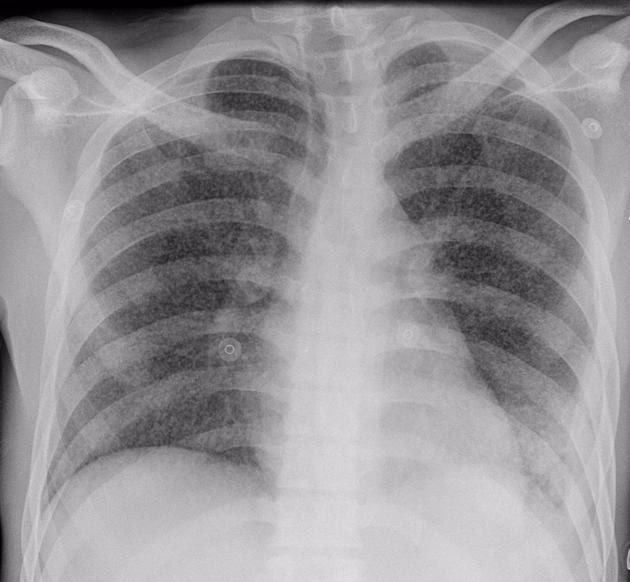

Det er netop i vigtigheden af fortsættelsesfasen, at vi finder kernen i problemet med for tidligt afbrudt behandling. Selvom en patient føler sig rask, og røntgenbilleder af lungerne ser normale ud efter 2, 3 eller 4 måneder, lurer de skjulte bakterier stadig. At stoppe behandlingen før tid er som at slukke en ildebrand, før alle gløderne er væk. Det kan blusse op igen, og ofte med større styrke.

- Få foretaget de rigtige tests: Insister på at få taget en opspytprøve, som kan sendes til både mikroskopi og dyrkning. Selvom dit røntgenbillede er normalt, kan der stadig være aktive bakterier. Et normalt røntgenbillede udelukker ikke aktiv TB.